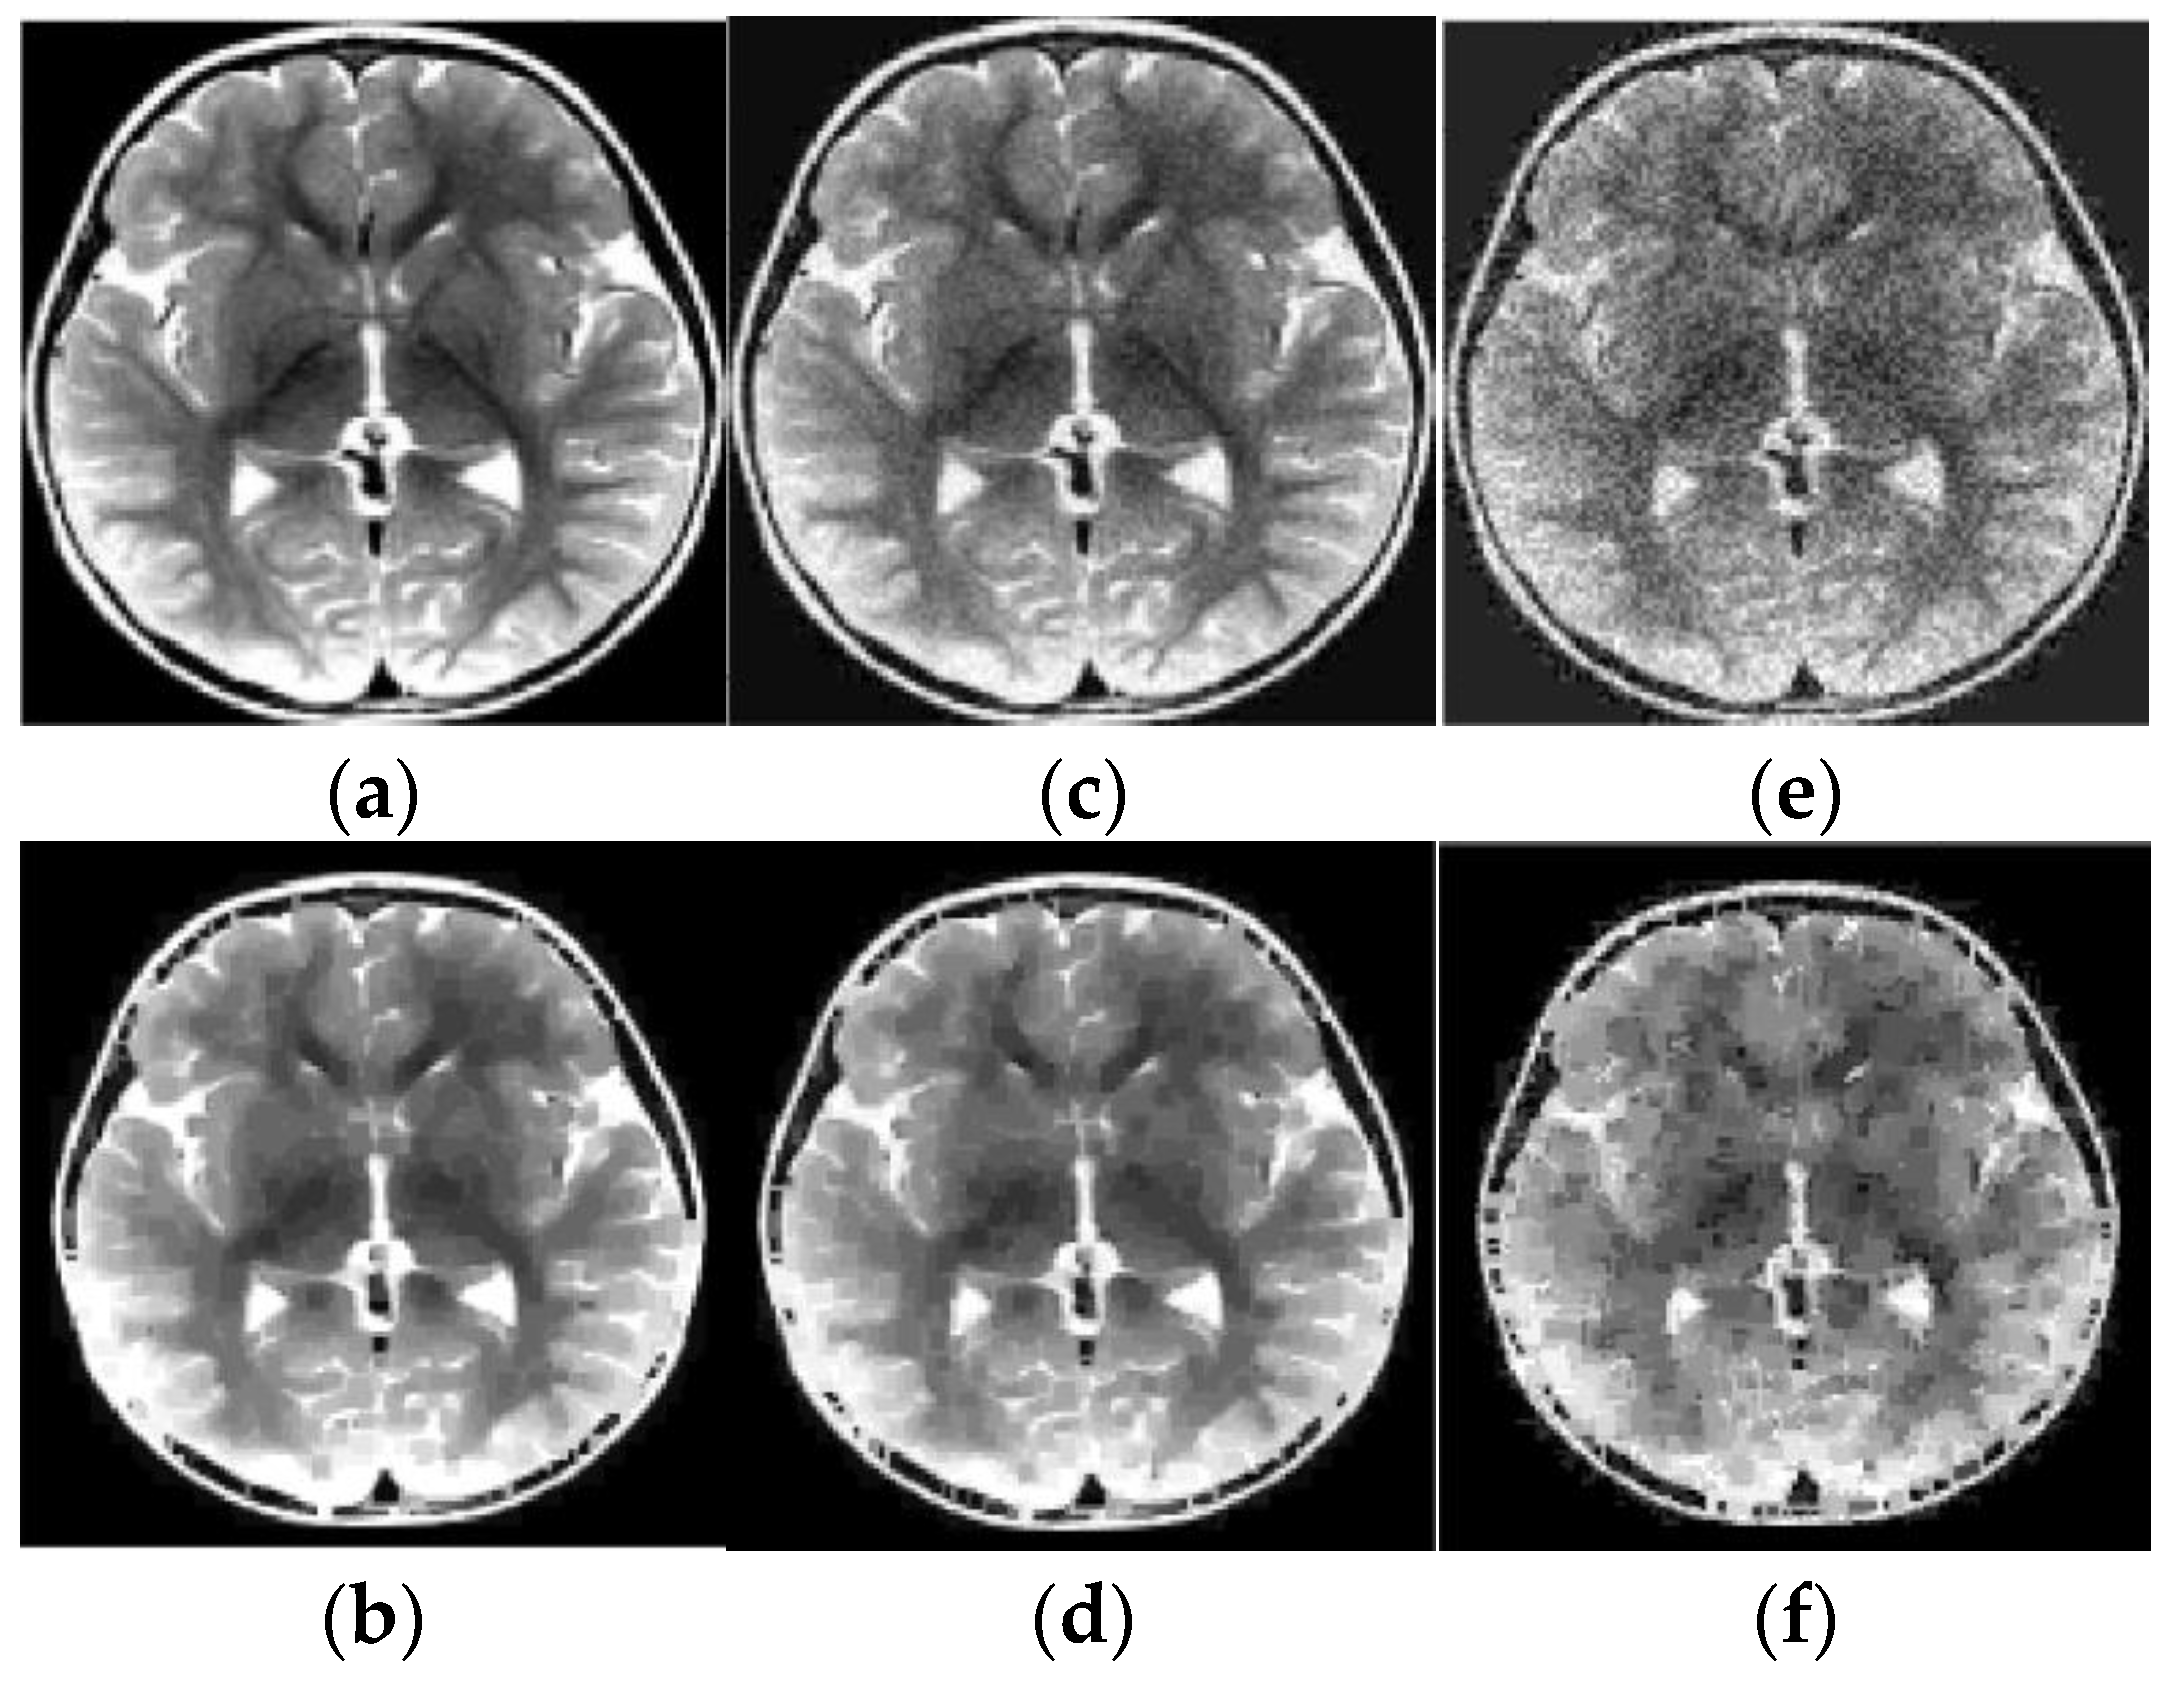

Results of reconstruction of MRI image based on qualitative data. (a) Original image; (b) Reconstructed image; (c) Original noisy image; (d) Reconstructed noisy image.

Figure 10.

Results of reconstruction of MRI human brain image based on qualitative data. (a) Original image; (b) Reconstructed image; (c) Original low noise image; (d) Reconstructed low noise image; (e) Original noisy image; (f) Reconstructed noisy image.

As before, the ER data were obtained using pixels squares that were scanned in each of 20 layers, and their scan period was 1 pixel. The SNR, which is defined for an average image intensity, is 9.7 dB (for Figure 9c), 23.3 dB (for Figure 10c), and 9.3 dB (for Figure 10e). Note that Figure 9d and Figure 10d,f also demonstrate the noise reduction ability of the reconstruction algorithm (15), (16), (27).

For example, these spots can be numerical intervals, and hence we can split the grayscale image into flat layers, corresponding to these intervals. Then one can reconstruct images in the layers independently and combine them again into the entire image. Results of the reconstruction are demonstrated in Figure 7, Figure 8, Figure 9 and Figure 10, where the intensity axes of pixels images were divided into 20 layers. The number of basis squares was about 20,000, and the calculation times were 6–9 min.